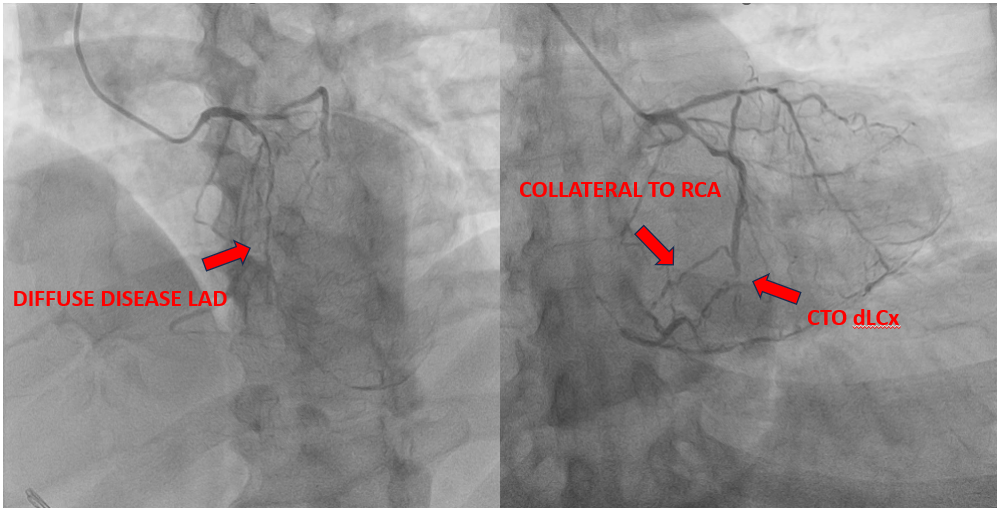

Coronary Angiography Findings

• The LM coronary artery was normal.

• The LAD artery showed diffuse severe disease with approximately 99% stenosis extending from the proximal to distal segment.

• The RCA was completely occluded, with collateral flow observed from the mid LCx to the RCA.

• The distal LCx was completely occluded.

• Collateral circulation from the mid LCx supplied the right coronary territory.